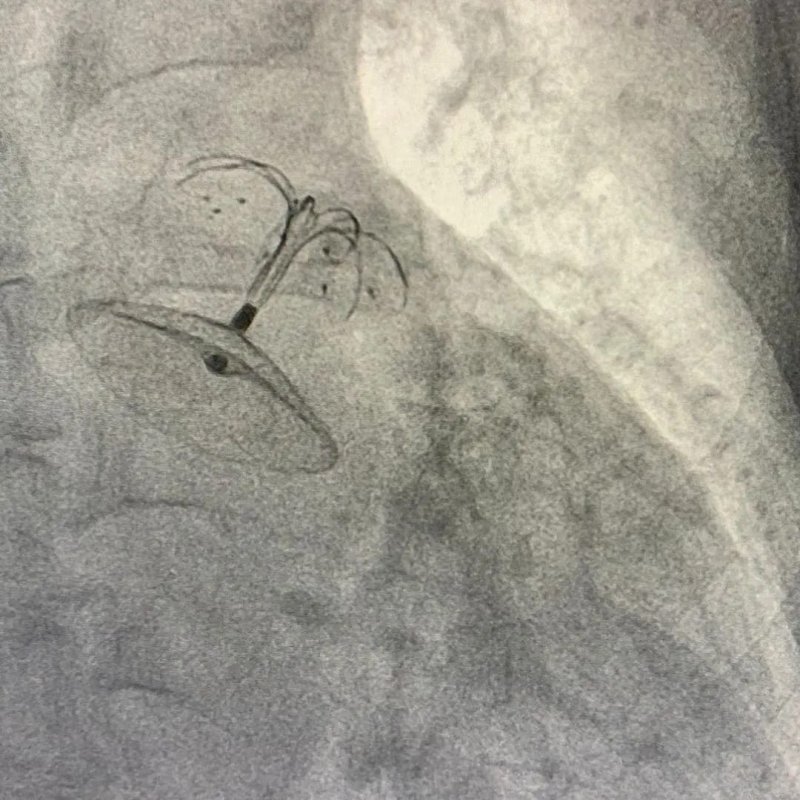

İnme ve kanama riski taşıyan hastalara uygulanan bu yöntemin Türkiye’de sadece belirli merkezlerde gerçekleştirilebildiğini ifade eden Tıp Fakültesi Kardiyoloji Ana Bilim Dalı Başkanı Doç. Dr. Servet Altay, bu yöntemi TÜ Hastanesi’nin ve kardiyoloji ana bilim dalının imkan ve kabiliyetleri ile başarılı bir şekilde uyguladıklarını dile getirdi. Ritim bozukluğu hastalarında kullanılan kan sulandırıcı ilaçların bazı riskleri beraberinde getirdiğini söyleyen Doç. Dr. Servet Altay, “Bazı hastalarımız da hem pıhtı hem de kanama riskini bir arada bulunuyor. Örneğin hastamız daha önce mide veya beyin kanaması geçirmiş. Bu tür hastalara kan sulandırıcı veremiyoruz ama hastada ritim bozukluğu da olduğu için inme geçirme riski var. Bu tür hastalar için geliştirilen yenilikçi bir yöntem uygulanmaya başlandı. Hastanın kasığından kalbin sol kulakçık bölgesine girerek şemsiye yöntemi ile o bölgeyi kapatıyoruz. Birkaç ay sonra ise kalbin şemsiye ile kapattığımız o bölgesi vücudun, kendi dokusu ile tamamen kaplanarak hasta sağlığına kavuşmuş oluyor. Böylece hasta için inme riski de ortadan kalkmış oluyor. Hastanın kan sulandırıcı ilaçlar kullanmasına da gerek kalmadığı için kanama riski de taşımıyor artık hasta” dedi.

Sol atriyal apendiks kapatma isimli yöntemin kompleks bir uygulama olduğu için sadece belirli merkezlerde yapılabildiğini ifade eden Altay, “Böylesine kompleks bir işlemi Üniversitemizde başarıyla gerçekleştirmiş olduk. Bu işlemde en önemli hususlardan biri 3 boyutlu eko-kardiyografi cihazını kullanmış olmamız. Doç. Dr. Muhammet Gürdoğan hocamız bize bu konuda destek verdi. Kalbe bıraktığımız şemsiye dediğimiz cihaz kısa bir süre içerisinde vücut dokusu ile birleşiyor. Tüm bu işlemlerle hastanın konforunu bozmadan, yaşam standartlarını düşürmeden, herhangi bir yara izi bırakmadan küçük bir kesi ile sağlığına kavuşturmuş olduk” diye konuştu.

Hastanın tanı, teşhis ve tedavi yöntemleri hakkında bilgiler veren TÜ Tıp Fakültesi Kardiyoloji Ana Bilim Dalından Dr. Öğr. Üyesi Murat Gök, “Hastamız, 67 yaşında bir kadındı. Hastamızın ritim bozukluğu tanısı mevcuttu. Ek risk faktörlerinin yanı sıra kadın olması nedeniyle mutlaka kan sulandırıcı ilaç kullanması gerekiyordu. Fakat hastanın yemek borusu bölgesinin uç bölümünde damar genişlemesi olduğu ve kan sulandırıcı ilaçlar kullandığı için daha önce 3 defa da kanama öyküsü olan bir hastaydı. Hastamızın, Gastroenteroloji Bilim Dalı tarafından takip ve tedavisi yapılıyordu. Hastanın durumunu birlikte değerlendirdiğimizde kan sulandırıcı ilaçlar kullanmasının risk teşkil ettiğine karar verdik ancak hastanın kardiyolojik yönden de mutlaka kan sulandırıcı ilaçlar kullanması gerekiyordu. Çünkü hastada mevcut olan ritim bozukluğu, felç durumuna neden olan risk faktörlerinin başında geliyordu. Sorunu nasıl çözebileceğimizi düşündük ve kalpte pıhtıya sebebiyet veren bölge olan apendiks bölgesini kapatmaya karar verdik. Böylece hastanın kan sulandırıcı ilaç kullanmasına gerek kalmadan hem mevcut kanamaya sebep olabilecek riskleri hem de inme riskini ortadan kaldırmış olduk. Bu uygulamayı anestezi eşliğinde yaptık ve 2 saat sonra hastayı uyandırdık. Gerekli takip ve kontrollerin ardından hastamızı bir iki gün içinde taburcu edeceğiz” ifadelerini kullandı

Kalp ultrason cihazlarının yıllardır kullanıldığını fakat bunların 2 boyutlu düzeyde kaldığını söyleyen TÜ Tıp Fakültesi Kardiyoloji Ana Bilim Dalı Öğretim Üyesi Doç. Dr. Muhammet Gürdoğan, 3 boyutlu ekokardiyografi yöntemlerinin son zamanlarda kullanılmasıyla kalbin cerrahların gördüğü şekliyle görülmesinin sağlandığını ifade etti. TÜ Hastanesi’nde de 3 boyutlu ekokardiyografi yönteminin başarı ile kullanıldığına dikkat çeken Gürdoğan, “Hem operatör arkadaşlarımızın cerrah gözüyle daha net bir görüntü sağlaması, işleme kılavuzluk etmesi ve işlem sonrası takılan şemsiyenin kontrol edilebilmesi noktasında bizlere yol gösteren, gelişmişlik düzeyi yüksek bir görüntüleme yöntemi. Biz ekip arkadaşlarımızla birlikte bu işlemi başarılı bir şekilde gerçekleştirmiş olduk. Hastamız artık kan sulandırıcı ilaç kullanmak zorunda değil. Böylece kanama riskini de ortadan kaldırmış olduk” dedi.